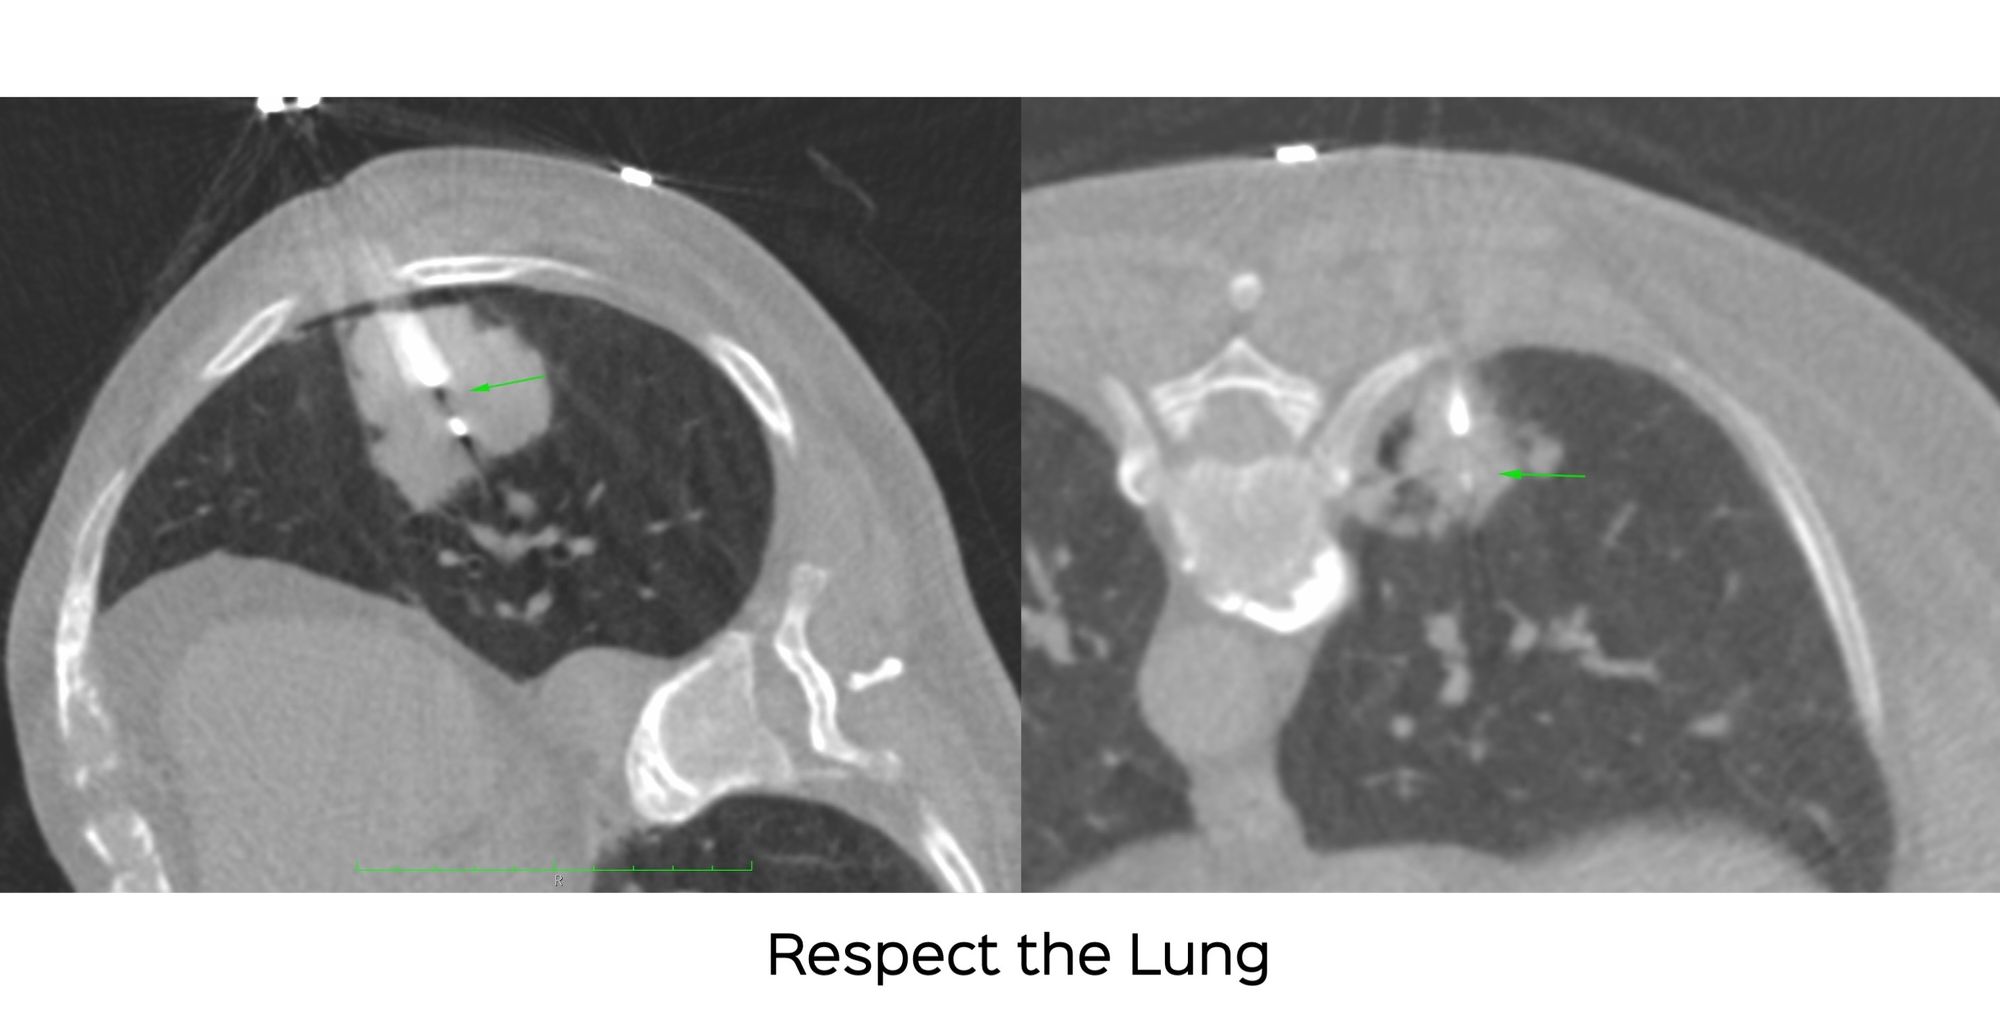

Case 8: Respect the Lung - A Tale of Two Biopsies and Complications